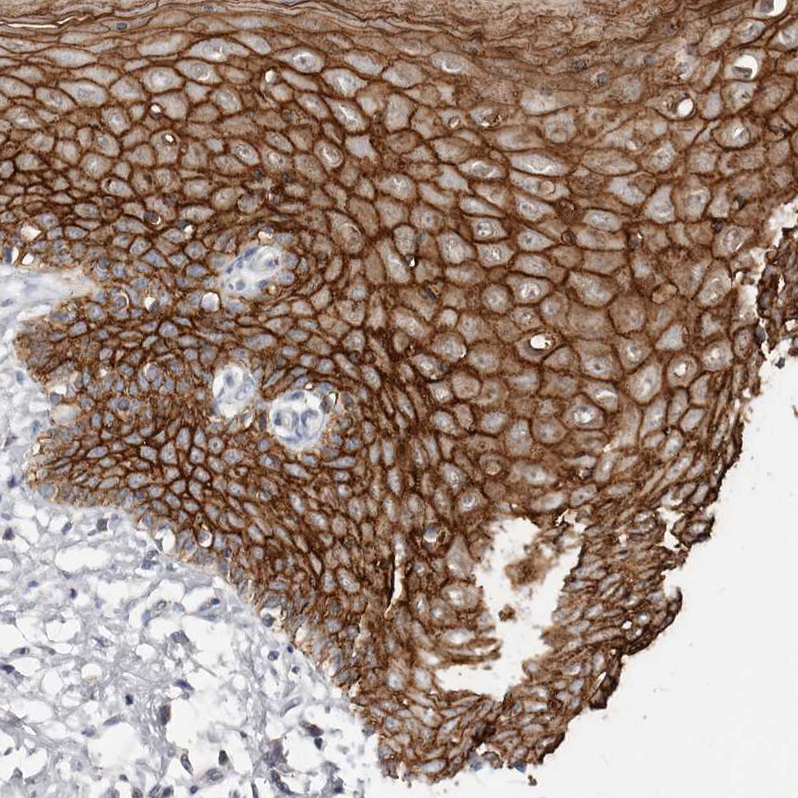

Immunohistochemistry analysis in human esophagus and liver tissues using HPA027613 antibody. Corresponding S100A14 RNA-seq data are presented for the same tissues.